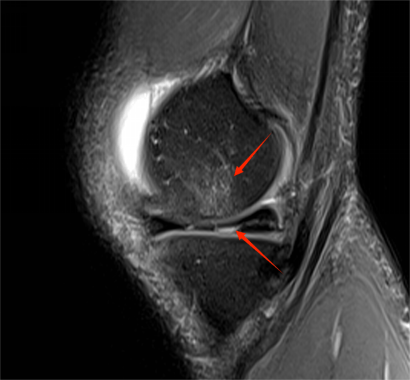

△ 跳绳之后交叉韧带撕裂

△ 跑步之后造成的骨髓水肿和半月板撕裂